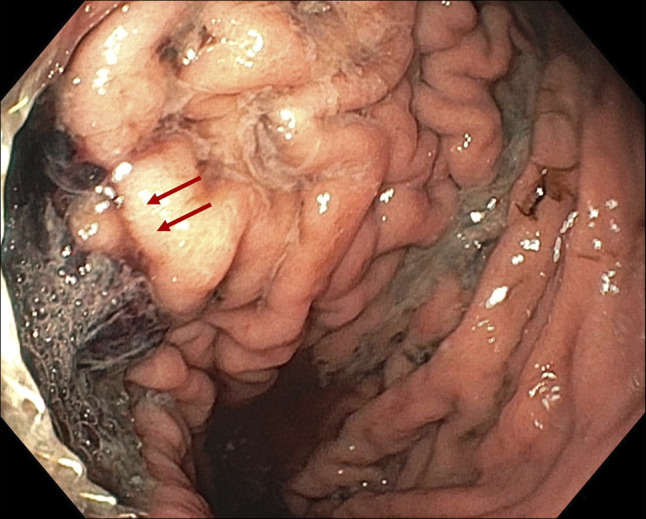

管腔旁置金属支架(LAMS)已被用于胰周收集物的引流,尽管它们可能伴有并发症,包括出血。我们报告一个49岁的男性病人,他出现呕血和晕厥后三周半的LAMS放置胰腺周围收集引流。计算机断层扫描显示脾动脉被支架远端法兰侵蚀。切除LAMS前行脾动脉栓塞术,3天后行脾切除术。患者在两年的随访后仍无症状。本病例展示了一种治疗罕见但可能致命的LAMS并发症的方法。

Lumen-apposing metal stents (LAMS) have been used for drainage of peripancreatic collections, although they may be associated with complications, including bleeding. We report a case of a 49-year-old male patient who developed hematemesis and syncope three and a half weeks after LAMS placement for peripancreatic collection drainage. A computed tomography scan revealed splenic artery erosion by the distal flange of the stent. Splenic artery embolization was performed before LAMS removal, and splenectomy was required 3 days later. The patient remains asymptomatic after two years of follow-up. This case demonstrates an approach to a rare but potentially fatal complication of LAMS.